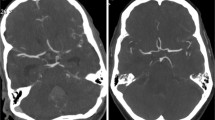

Representative cases are shown in Figs. 2, 3, and 4. Figure 2 shows the case of a 71-year-old woman with a left MCA aneurysm who underwent BSCTA under both the 120-kVp and the 80-kVp protocols after 6 months. Although the radiation and the CM doses of the 80-kVp scans were substantially lower than those in the 120-kVp protocol (CTDIvol: 14.8 vs 41.8 mGy; CM dose: 51 vs 65 ml), the image quality of the 80-kVp scan was better than that of the 120-kVp scan. Figure 3 shows the 80-kVp images of a 73-year-old woman who had undergone clipping of a right ICA aneurysm (CTDIvol: 16.4 mGy; CM: 38 ml). Arteries around the skull base and clip were obscured on the non-subtraction images. They were clearly depicted on subtraction images without severe clip-induced artifacts or confounding contrast enhancement of the cavernous sinus. Figure 4 shows the 80-kVp images of an 81-year-old woman with a clipped left MCA aneurysm (CTDIvol: 16.2 mGy; CM: 32 ml). The ICA at the level of the skull base and the aneurysm remnant at the left MCA, obscured on the non-subtraction image, were clearly depicted on the subtraction image.

Volume-rendered (VR) images of an 81-year-old woman with a clipped left MCA aneurysm. Scanning was with the 80-kVp protocol (iopamidol-370, 32 ml; CTDIvol, 16.2 mGy). The upper and lower rows show the right anterior oblique and inferior views, respectively, of the non-subtraction CTA (left) and subtraction CTA with clip (middle) and without clip (right). The ICA at the level of the skull base and the aneurysm remnant at the left MCA, obscure on the non-subtraction image, was clearly depicted on subtraction images